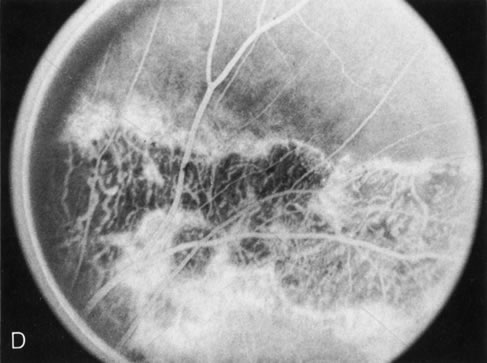

FA plays an important role in the understanding of this rare disorder. In the earliest manifestations of the disease, FA shows a single, isolated choroidal neovascular membrane unassociated with other causes of a membrane, such as drusen or angioid streaks (Fig. 13).25 Presumably this membrane is the cause of the subsequent hemorrhagic maculopathy with secondary disciform scarring, occurring initially in the macula but often extending throughout the retina.

Fig. 13. Hereditary hemorrhagic macular dystrophy (pseudoinflammatory macular dystrophy of Sorsby). Fluorescein angiography in this family member demonstrates that the earliest finding is an isolated choroidal neovascular membrane B). Despite laser photocoagulation, a hemorrhagic maculopathy developed in this eye (C, D) and eventually a disciform scar (E) formed, as it had in the fellow eye, and in the eyes of other affected family members.

Abnormal choroidal perfusion, manifested on FA as a delay in choriocapillaris filling, has been seen in the restudy of some of Sorsby's initial pedigrees.26 This unusual pattern has been related to the histopathologic finding of a “confluent, lipid-containing, amorphous deposit found between the basement membrane of the RPE and the inner collagenous layer of Bruch's membrane.”27